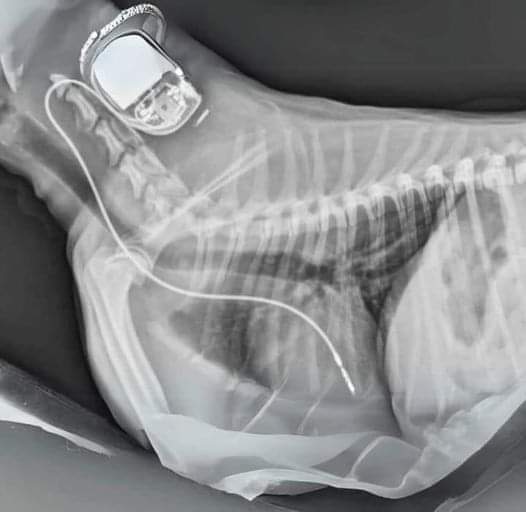

Did you know that if you have a pacemaker, you can include it in your Will to be donated to a dog in need after you pass away?

Although pacemakers cannot be used for another human, they can help dogs with heart problems and potentially save their lives. You can arrange for the pacemaker to be sent to a vet of your choice.

Many pacemakers are simply thrown away, and dogs may die because people do not know about this option. Donating the pacemaker can even save the dog's owner the cost of a new one, which can sometimes make a crucial difference in affording life-saving treatment.